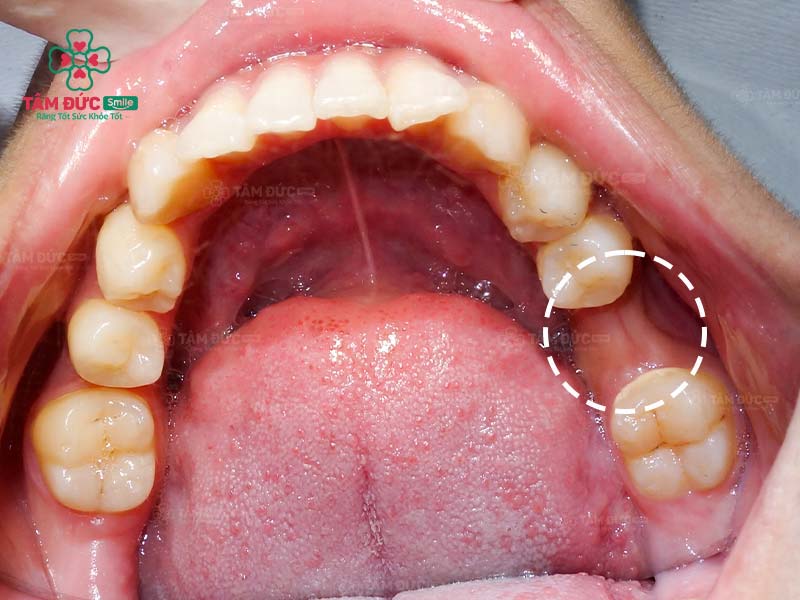

Khi một chiếc răng bị mất, xương hàm ở vị trí đó bị mất đi. Để bù đắp cho sự thiếu hụt này, xương hàm ở các vị trí kế cận có xu hướng di chuyển về phía răng đã mất. Quá trình di chuyển của nó làm cho mật độ xương ở đây bị thưa và xốp hơn.

Ngoài ra, xương hàm cũng phát triển và được duy trì nhờ vào hoạt động ăn nhai hàng ngày. Khi răng thật mất đi, xương hàm không còn nguồn kích thích (từ lực nhai), làm xương hàm dần dần bị tiêu biến.

Xương hàm bị tiêu biến, mỏng đi sau khi mất răng